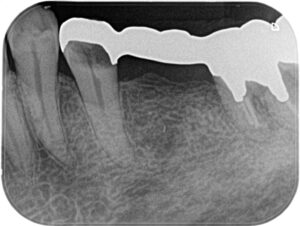

(画像:before_rc1.jpg 治療前の下顎小臼歯。歯ぐきの腫れが見られます)

治療前後の比較

Before/After X線写真

痛みの改善と再発防止

治療後、患者さまからは「噛んでも痛みがなくなった」「歯ぐきの腫れが再発しなくなった」と喜びの声をいただきました。